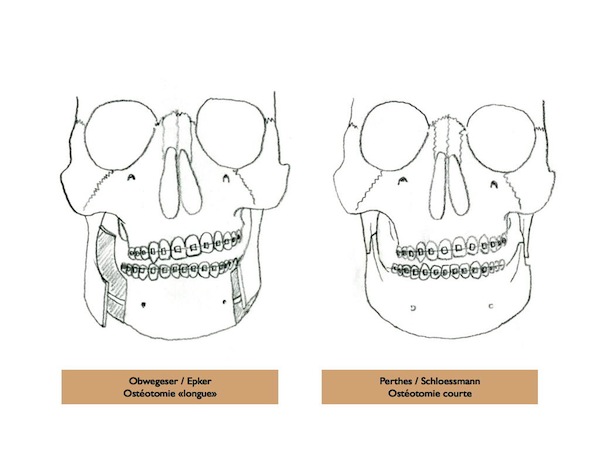

La technique classique est une ostéotomie Basse et longue, le long du nerf alvéolaire inférieur. C’est l’ostéotomie d’Epker, modifiée par Obwegeser. Elle présente pour inconvénient principal d’entrainer une perte de la sensibilité de la lèvre. Par ailleurs, parfois le bord osseux est irrégulier, ce qui peut se voir, ou être inconfortable dans certaines positions.

Il existe donc trois techniques d’ostéotomies mandibulaires :

Les deux premières (Obwegeser et Epker) se ressemblent. La technique d’Eplker est une évolution de la première. Elles présentent toutes les deux l’inconvénient de se réaliser le long du nerf alvéolaire inférieur, et d’entrainer une hypoesthésie partielle dans certains cas (7 à 67% des cas selon les séries).

Ostéotomies Basses

Les ostéotomies basses peuvent être intéressantes dans certaines asymétries horizontales, mais augmentent le risque de troubles de la sensibilité de la lèvre en post-opératoire. Par ailleurs, elles ne permettent pas d’abaisser l’angle de la mandibule dans les asymétries verticales, et une décalage osseux du bord inférieur peut être gênant.

Ostéotomies Hautes

L’ostéotomie Haute de la mandibule est plus courte et diminue donc le risque d’atteinte du nerf alvéolaire inférieur (qui détermine la sensibilité de la lèvre inférieure). Elle permet également de remonter ou d’abaisser l’angle de la mandibule, sans que le décalage osseux ne puisse être visible ou palpable. Il s’agit d’une technique mini-invasive dont les suites sont simples.

La technique chirurgicale a été décrite décrite par Perthes Schliessmann en 1932. Il s’agit de l’ostéotomie mandibulaire Haute, ou courte, ou sus-spigienne. La plus grande difficulté est technique, puisque l’ostéosynthèse est très haute. Le tournevis contre-angle de Fritzemeier permet de limiter la taille de l’incision. Cet instrument permet de réaliser une chirurgie mini-invasive.